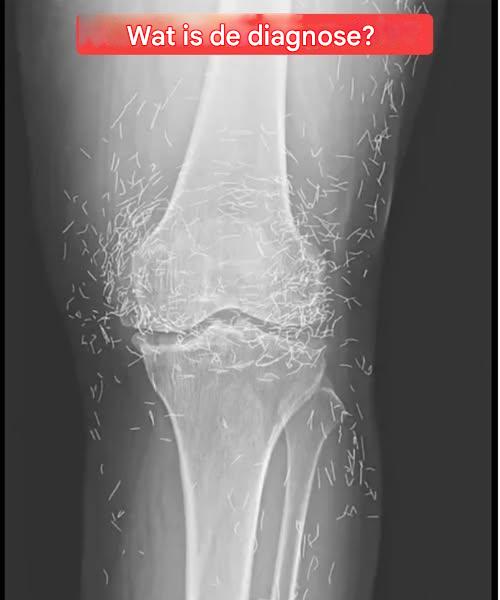

Röntgenfoto onthult honderden gouden naalden in knieën van vrouw

Toen artsen een röntgenfoto bekeken van de knieën van een oudere vrouw die leed aan ernstige gewrichtspijn, ontdekten ze een goudmijn: honderden kleine gouden acupunctuurnaaldjes die in haar weefsel waren achtergebleven.

Tijdens de acupunctuurbehandeling van de vrouw werden de naalden, waarvan men dacht dat ze van goud waren, opzettelijk in haar weefsel gelaten om voortdurende stimulatie te bewerkstelligen, aldus het rapport.